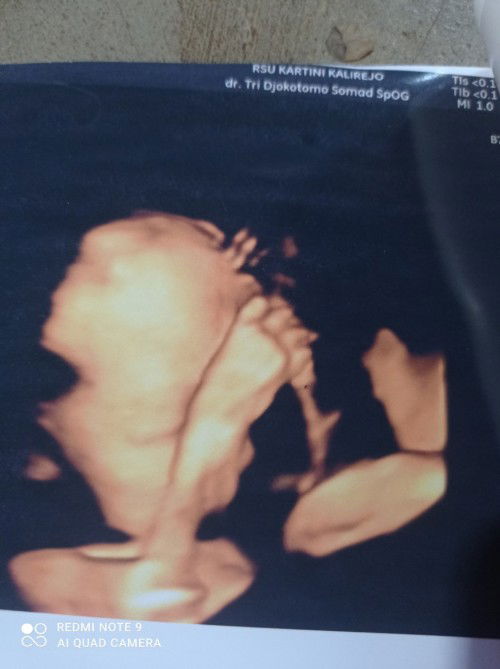

Bunda ada ga disini yg hamil udh 40w blm juga lahir debay nya,, dulu kehmilan sbelum ny aq maju 8 hari dr hpl,, ini dh lewat 2 hr kmren sih kata bidan ny sruh nunggu seminggu lg klo blm ad tnda2 jg baru d ksih rjukan ke dokter,, jd kwatir nih bund tiap hari, mrsa cemas, panik, stres, sdangkan seangkatan aq dh lhir smua,, pdhal senam, jln kaki, berbgai grakan, hb udh d lkuin smua, tp ttep utunnya anteng, hrus sbar dlu x ya bund .. Tp ttep aja kpikiran, walupn hrus rilex sih ktanya.... Bntu jwab donk#seriusnanya